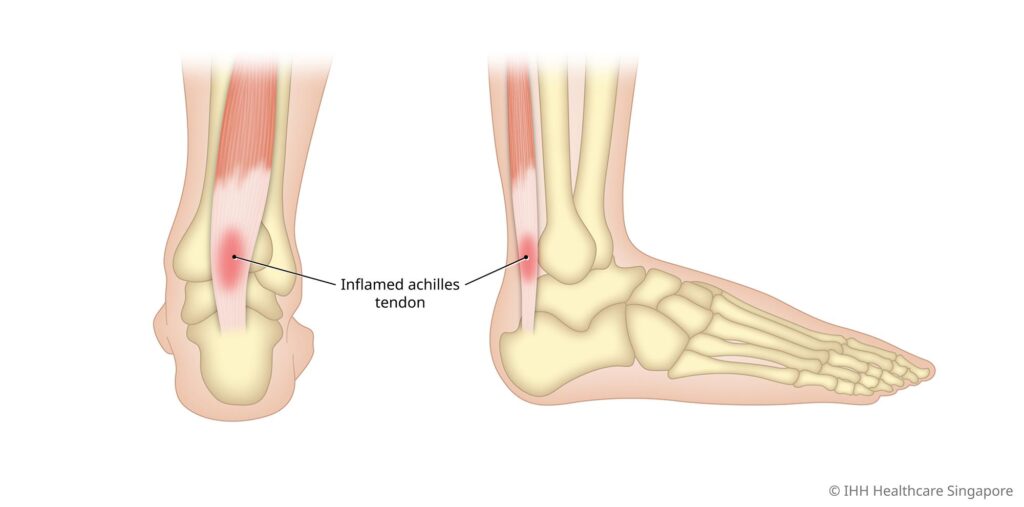

What Is Achilles Tendonitis?

Achilles tendonitis refers to the inflammation of the Achilles tendon, the largest tendon in the body located at the back of the ankle that connects the calf muscles to the heel. This condition often results from repetitive stress or overuse and is common in athletes, particularly those who run or jump frequently. It can cause pain, stiffness, and swelling in the tendon, especially during physical activity or when pressure is applied.

Symptoms of Achilles Tendonitis

Achilles tendonitis typically causes the following symptoms:

- A tightness and/or burning pain at the start of activity along the tendon, which eases during activity but worsens afterward, particularly when walking, running, or jumping

- Stiffness in the tendon, especially first thing in the morning, after prolonged sitting, or at the beginning of exercise.

- A limp

- Pain, stiffness, and loss of strength in the affected area.

- A visible bump or swelling either in the tendon or right behind the heel bone.

- Irritation from shoes rubbing against the bump, with some patients experiencing relief when wearing backless shoes.

- Reduced pain when wearing shoes with a slight heel compared to flat shoes.